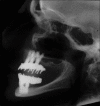

Figure 1

Lateral cephalograph showing fixed implant prostheses ad modum Brånemark on six implants in the anterior part of each jaw. No posterior implants but cantilevers supporting the prostheses to the first molar